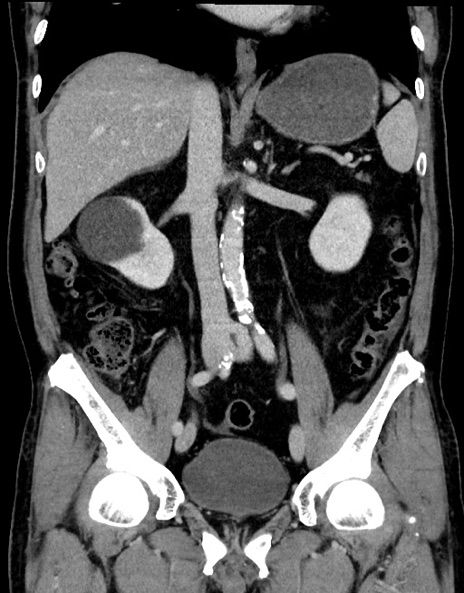

症例15(冠状断像)

【症例】70歳代男性

【主訴】腹痛

【現病歴】今朝から腹痛あり。全体的に痛い。特に左上の方。排ガスが今日はない。冷や汗が出る。

【既往歴】直腸癌術後

【身体所見】左側腹部〜上腹部に圧痛あり。腹膜刺激症状明らかなではない。軽度反跳痛。左下腹部に術後瘢痕あり。

【データ】WBC 7700、CRP 0.02